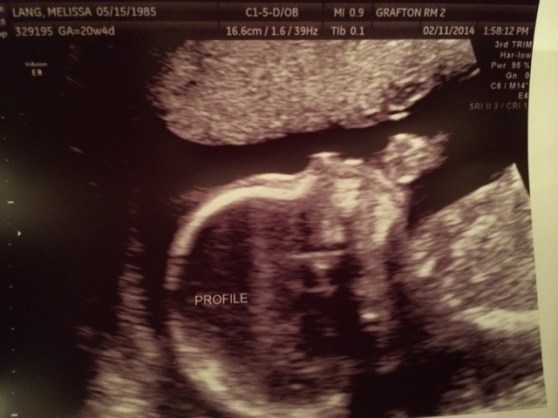

Here’s a shot of the little one’s lady parts from underneath. Notice the two legs, tush and three little labia reflection lines.